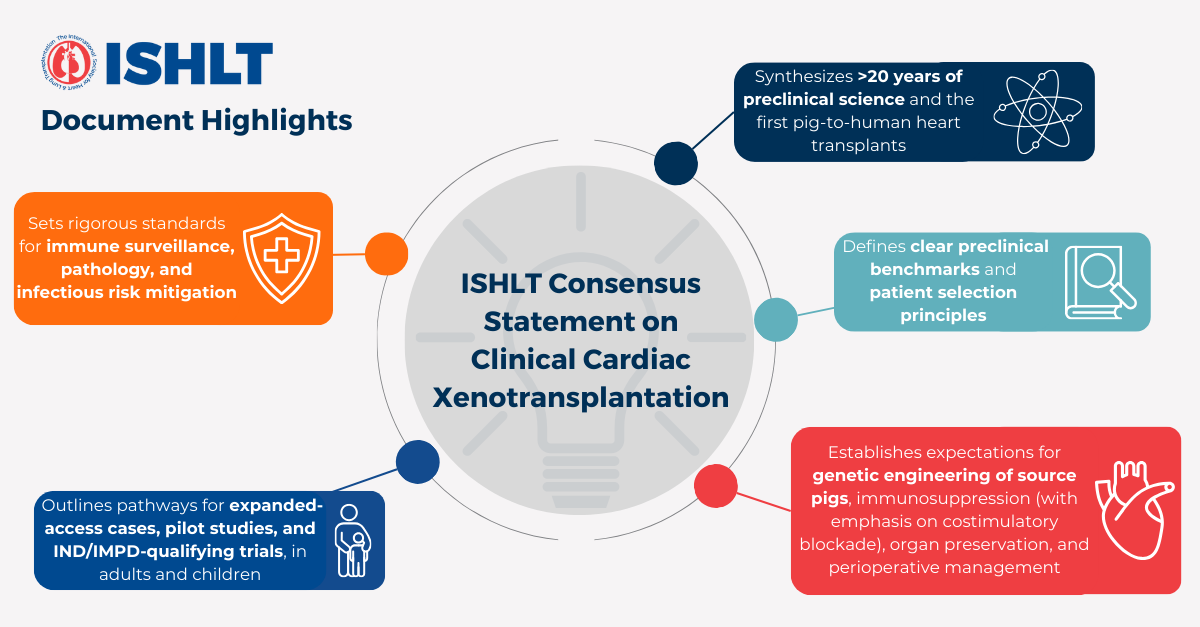

In 2025–2026, the International Society for Heart and Lung Transplantation (ISHLT) published a consensus statement that lays out strict guidelines for clinical cardiac xenotransplantation. These include:

- Which human antirejection drugs are acceptable?

- How to monitor for rejection and infection?

- How to manage informed consent and long-term follow-up?

This document is essentially a “blueprint” for bringing pig‑heart transplants out of the emergency room and into structured clinical practice.

International Society for Heart and Lung Transplantation document on rules for patient selection, immunosuppression, and monitoring in pig‑heart xenotransplants. 20 February 2026.